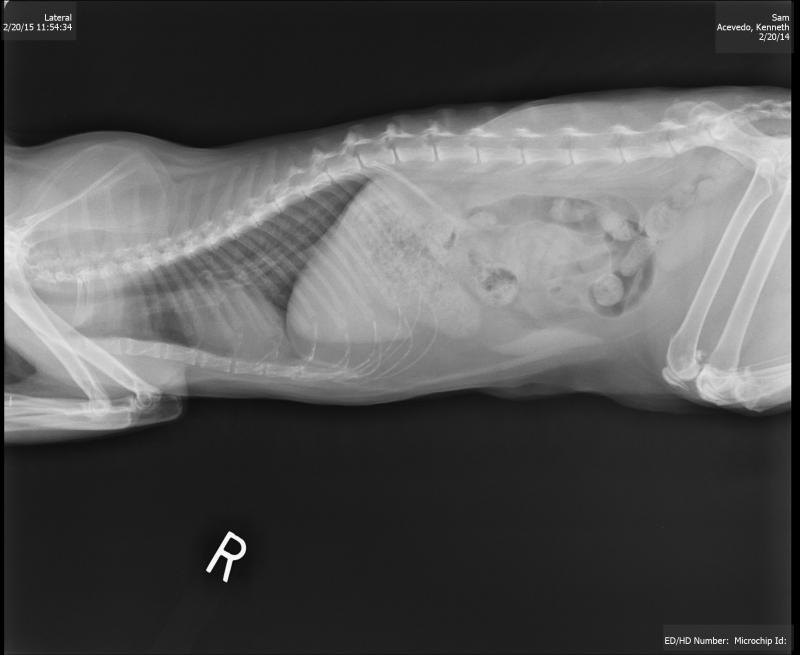

Radiographic view canine patient...abdominal.